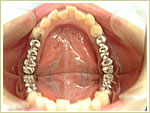

●すべての歯を失った場合

79歳 男性 インプラント埋入数:12本 画像拡大

治療前

治療中

参考写真

治療後

治療中治療後